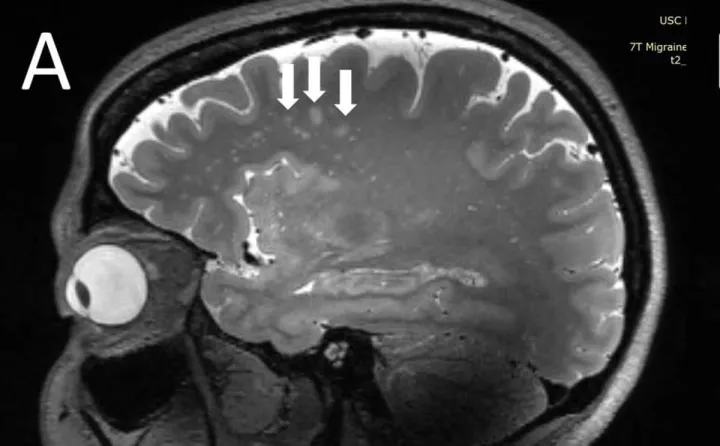

Точки скопления белков при мигрени. Точки скопления белков при мигрени.© Копенгагенский университет

Этот процесс активирует тройничный нерв в основании черепа, который связывает периферическую нервную систему с головным мозгом. Спинномозговая жидкость попадает в основание тройничного нерва, тем самым провоцируя симптомы ауры и последующий приступ боли. А конкретный участок головы болит из-за того, что именно в этом отделе накапливаются вышеупомянутые белки, которые создают очаг боли.